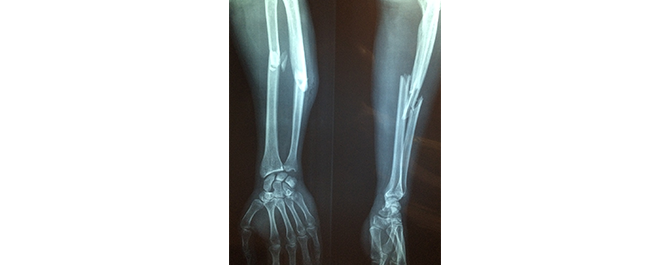

De påpekar också att frakturrisken är högre bland typ 1- än bland typ 2-diabetiker. Till exempel är höftfrakturer fem gånger vanligare bland typ 1-diabetiker.